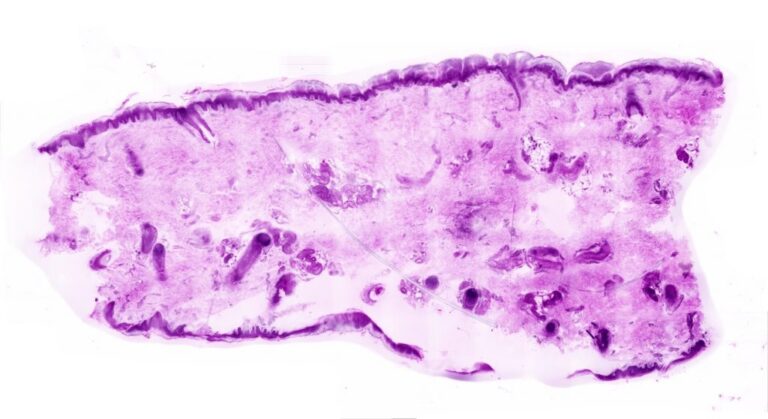

Diagnosing cancer directly in the operating room through sectioning-free histology

Histolution, a spin-off from Medical Laser Center Lübeck, has developed a microscope that utilizes laser technology to generate digital images of tumor samples directly within the operating room.